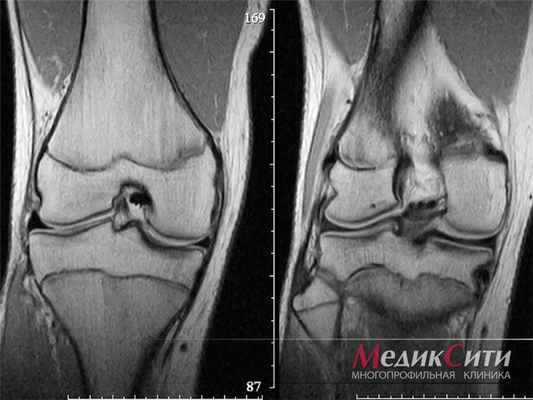

(Слева) Рентгенография в боковой проекции: определяется крупная (классическая) НОФ. Это поражение, имеет географический характер, расположено в метафизе, его основание находится в кортикальном слое кости. Отмечаются узкая зона перехода между поражением и интактной костью, склеротические края В и отсутствие периостальной реакции.

(Справа) Рентгенография в ПЗ проекции, этот же пациент: определяется классическая картина НОФ. Несмотря на его крупные размеры образование бессимптомно и не требует какого-либо вмешательства. Склероз вокруг внешних границ В поражения отражает его замещение нормальной костной тканью. (Слева) Рентгенография в косой проекции: визуализируются несколько НОФ с периферическим склерозом, что указывает на частичное их заживление. Множественные НОФ чаще всего наблюдаются при нейрофиброматозе.

(Справа) Рентгенография в боковой проекции: определяется бессимптомное поражение, основание которого расположено в кортикальном слое метафиза большеберцовой кости. Наблюдается частичное замещение поражения нормальной костной тканью. Отмечается достижение скелетной зрелости. Это поражение - типичная НОФ, в дальнейшем наблюдении нет необходимости. (Слева) МРТ (проводилась для оценки состояния менисков ), Т1ВИ, корональный срез: у этого же пациента подтверждаются ожидаемые внешние признаки НОФ - гипоинтенсивный центральный отдел и низкая интенсивность сигнала (соответствует интенсивности сигнала от кортикального слоя кости) в области заживления.

(Справа) МРТ Т2ВИ в режиме подавления сигнала от жира, аксиальный срез: у этого же пациента определяются все еще активный гиперинтенсивный компонент НОФ В и выражено гипоинтенсивный сигнал в периферическом заживающем его компоненте. Это поражение имело наиболее типичное для НОФ течение: после достижения пациентом скелетной зрелости произошло замещения поражения нормальной костной тканью.